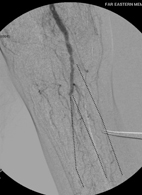

小腿本有三條主要動脈(在三條虛線所標示處),現在一條都看不到了!患者因而足部壞死、潰爛。